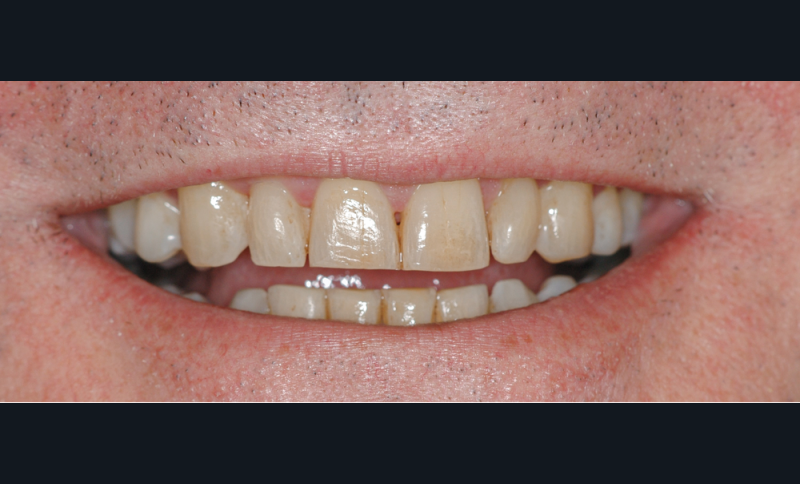

Le patient

- 54 ans

- Parodontite traitée en 2015 stabilisée, puis plusieurs épisodes d’activation sur les dernières années

- Prise en charge de son occlusion par une occlusodontiste et une orthodontiste (durée 3 ans)

- Hygiène orale perfectible

- Sportif et aucune consommation de tabac

- Suivi parodontal et péri-implantaire tous les

4 à 6 mois suivant les années